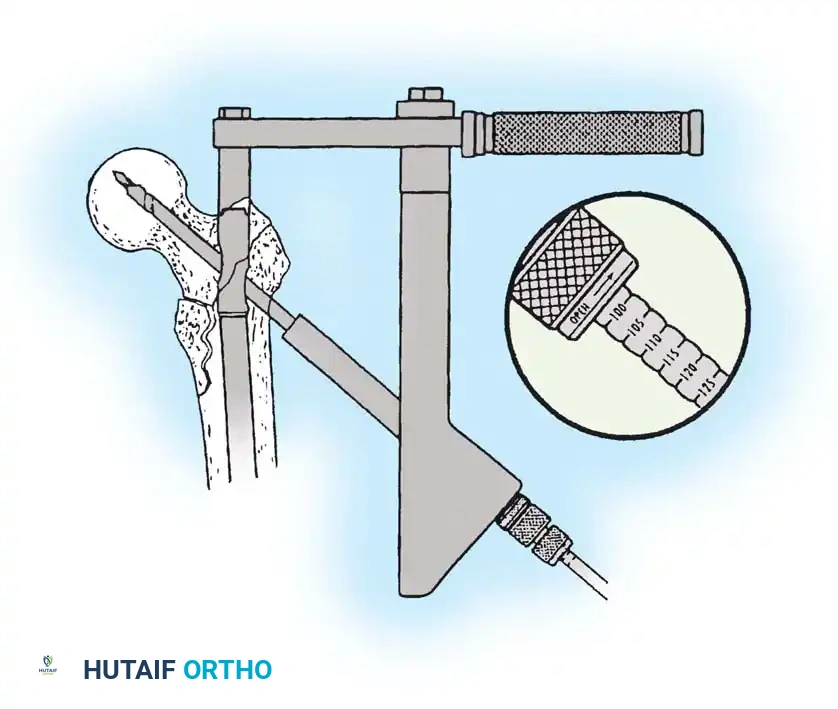

3. Guide Wire Placement

Whether using an SHS or a CMN, accurate placement of the guide wire into the femoral head is the most critical step of the operation.

Insertion of the guide wire. The wire must be positioned centrally in the femoral head on both AP and lateral views.

The Tip-Apex Distance (TAD):

Described by Baumgaertner, the TAD is the sum of the distance from the tip of the lag screw to the apex of the femoral head on both the AP and lateral radiographs. A TAD of less than 25 mm is strongly predictive of successful fixation; a TAD > 25 mm significantly increases the risk of screw cut-out.